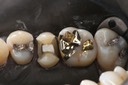

Wayne Chin #14 caries removal